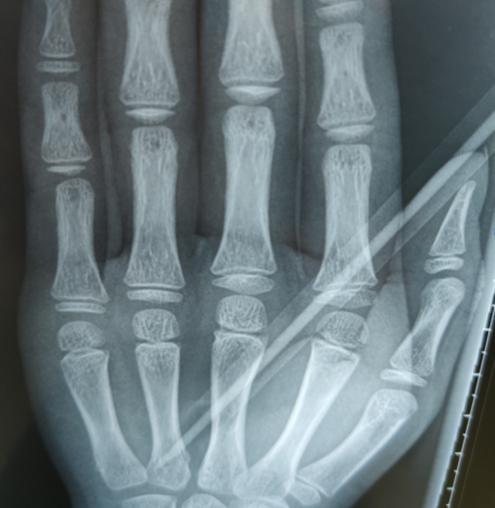

淼淼的妈妈和老师带着淼淼下午两点多才赶到我院,接诊的手外科三病区的李刚医生发现,铅笔斜着刺进淼淼的掌心2厘米,万幸的是没有造成“贯穿伤”。

李刚医生手术团队立刻为淼淼进行了手术,术中探查见其血管、神经、肌腱已经部分损伤了。手术团队延长切口,小心取出铅笔,在显微镜下修复损伤的血管、神经和肌腱,并打上石膏。